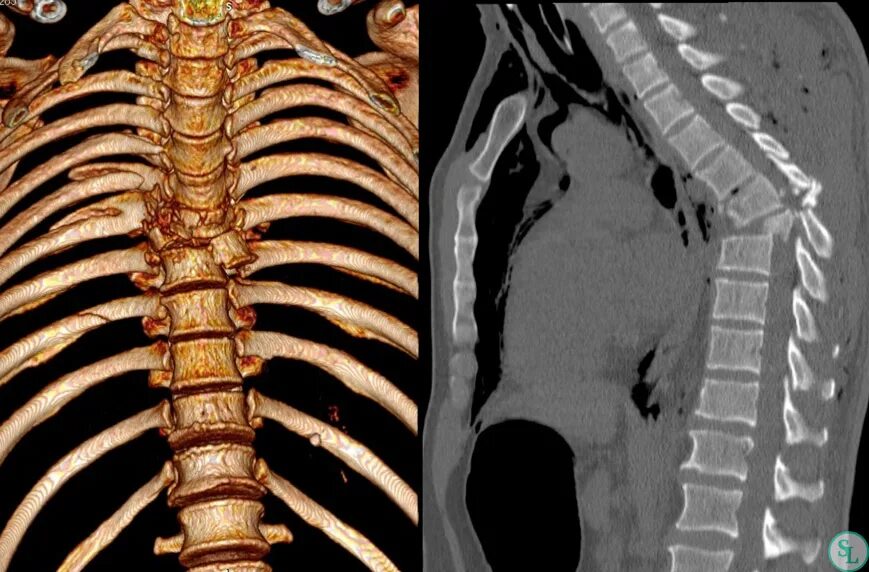

Перелом грудного позвонка код